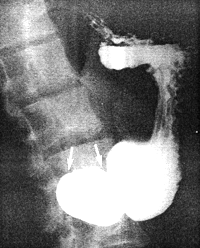

![]() |

| Fig. 13.3. Radiograph showing living anatomy. Two fine, flexible metal wires (retouched) are attached to serosal surfaces of lesser and greater curvatures. The space between the wires and intraluminal barium indicates the cylindrical muscular contraction |

Narrow, circumferential indentations of the barium column appeared in the body of the stomach and proceeded to move in a caudal direction. Opposite the indentations the fine, flexible wires remained in their original position, showing that these indentations were due to contraction waves in the walls and not "falling together" of the walls. At a point 3.0 to 4.0 cm orally to the pyloric ring each wave became stationary, at the same time initiating a concentric, cylindrical narrowing of the barium column in the remaining part of the stomach, as far as and including the area of the ring. Again the wires were seen to remain in their original position. During a contraction the space between the wires and the luminal barium widened to approximately 8.0 to 10.0 mm all round, indicating an active, tube-like or cylindrical contraction of the muscular walls, 3.0 to 4.0 cm in length (Fig. 13.3). After a second or two of maximal contraction, the walls relaxed and the cycle was repeated.